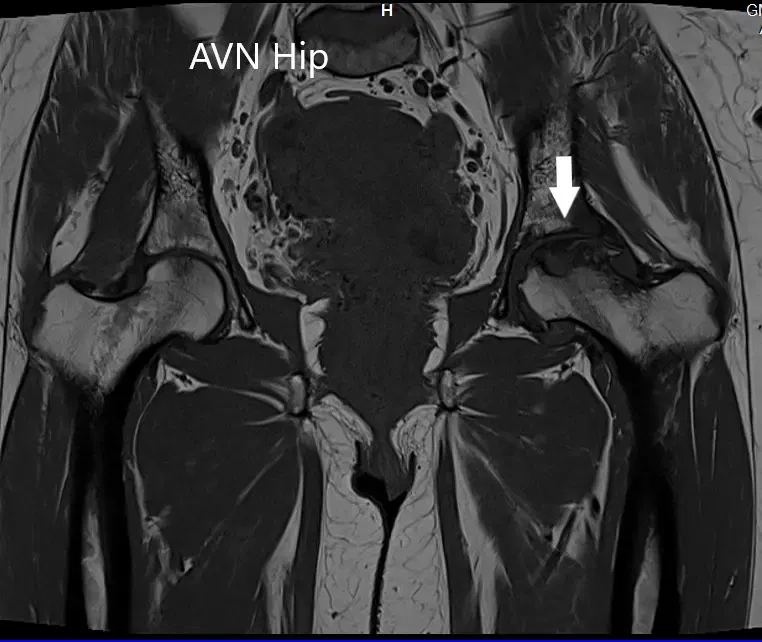

Se realizó una resonancia magnética que mostró una intensidad de señal alterada tanto en T1WI como en T2WI. Hubo un colapso sutil de la cabeza femoral izquierda. Se observó una línea sérpinosa e hiperintensa en T2WI que delimitaba una zona de osteonecrosis en la cabeza femoral izquierda. Esta zona afectaba al compartimento lateral y medial y cubría más del 50% de la superficie de la cabeza.

Se visualizaron cambios osteoartríticos secundarios en forma de reducción del espacio articular anterosuperior y formación de osteófitos. Se observó una pequeña cantidad de líquido en la cavidad articular.

Imagen T1WI de la resonancia magnética que muestra la sección coronal.